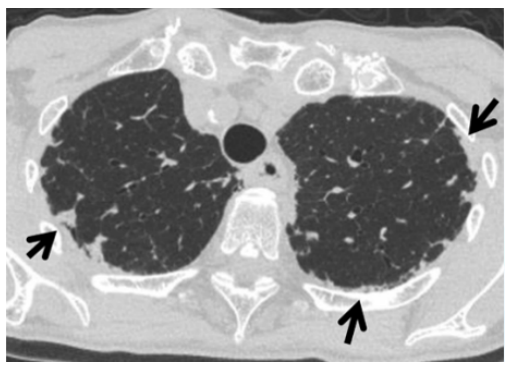

患者于2022年11月10日在全身麻醉下行左肺下叶部分切除+淋巴结活检术,手术过程顺利,入量1200 ml,尿量600 ml,出血10 ml。术后病理提示微浸润腺癌。术后顺利拔除气管插管,生命体征平稳。术后第3天开始出现活动后稍气喘,无明显发热,偶有咳嗽,咳白色黏痰。胸闷气喘症状逐渐加重。肝肾功能正常,D-二聚体正常,心肌标志物正常,未查血气和胸部CT;白细胞、CRP升高明显(表1)。予哌拉西林他唑巴坦+莫西沙星加强抗感染治疗。术后第5天胸部CT可见少量病灶(图2)。术后第12天胸部CT提示两肺间质性改变,右肺为著,局部可见支气管牵拉变形,磨玻璃影(图3)【普通感染不应出现如此变化,但当时并未引起重视】。后续患者出现呼吸衰竭,血气分析:pH 7.34,PaO2 53.1 mmHg,PaCO2 35.1 mmHg(面罩吸氧10 L/min)。转至ICU进一步治疗。